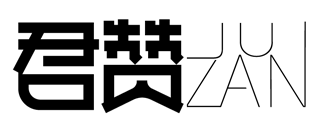

Immunohistochemical analysis of paraffin-embedded Human Colon Carcinoma Tissue using HSP40 Rabbit pAb diluted at 1:200